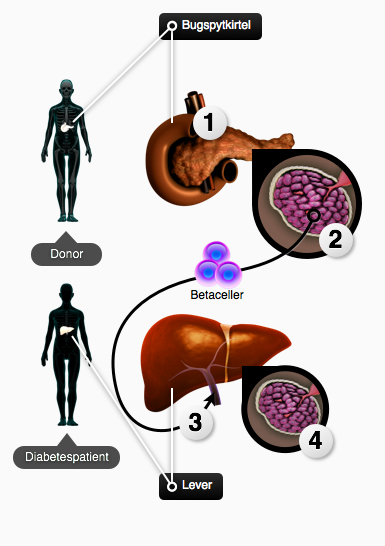

Ved celleterapi af diabetes, indsprøjtes betaceller (eller Langerhanske øer: klumper af betaceller) i portalvenen, der leder blod fra indvoldene til leveren, hvorefter de sætter sig fast i små klumper i leveren. Selv om betacellerne ikke sætter sig i bugspytkirtlen, hvor de normalt sidder, vil de stadig udføre deres funktion: udskille insulin, når blodglukosen er høj. Det er lykkedes at lave celleterapi med betaceller fra hjernedøde donorer. Den første virksomme metode til dette kaldes Edmonton protokollen. Efter at patienterne har fået de nye betaceller, opretholdes der et normalt glukoseindhold i blodet, uden at patienten skal tage insulinindsprøjtninger – patienten er helbredt mht. blodsukkerregulering! Men patienterne skal til stadighed tage medicin, som dæmper immunsystemet, for at undgå en afstødning af det nye væv.

Figur 32. Celleterapi med betaceller fra en donor. (1) En rask bugspytkirtel fjernes fra en nyligt død eller hjernedød donor. (2) Betacellerne isoleres fra bugspytkirtlen, ved at bruge et enzym, der løsner alle cellerne fra hinanden. (3) De isolerede celler indsprøjtes i portalvenen på diabetes-patienten. (4) Betacellerne sætter sig fast i små klumper i leveren, ved de små forgreninger, der er på portalvenen. Herfra kan de udføre deres funktion: at opretholde blodsukkerbalancen, og dermed helbrede patienten for diabetes.